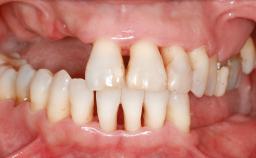

Ridge Preservation and Implant Placement for a Fixed Dental Prosthesis After a Car Accident

It is well known to clinicians that any removal of teeth will, over time, cause the dimensions of the alveolar ridge to be reduced by resorption of the bundle bone and by changes related to external modeling. This development is particularly evident in the crestal region with its thin buccal bone that consists of bundle bone almost entirely. The facial bone will rapidly resorb as blood supply from the periodontal ligament gets disrupted (Araújo and Lindhe 2005). There is no reason why traumatic tooth loss should not have the same consequences. It takes more than achieving implant osseointegration for a treatment outcome to be considered successful. No deficiency of bone or soft tissue is acceptable when an ideal esthetic outcome is the goal. Several articles (Sanz and coworkers 2011; Vignoletti and coworkers 2011) have reported on techniques of improving the alveolar ridge for implant treatment, notably focusing on protecting tissues from resorption.

Case Type Extended Space

Jaw Maxilla

Area Anterior|Posterior

# of Teeth 6